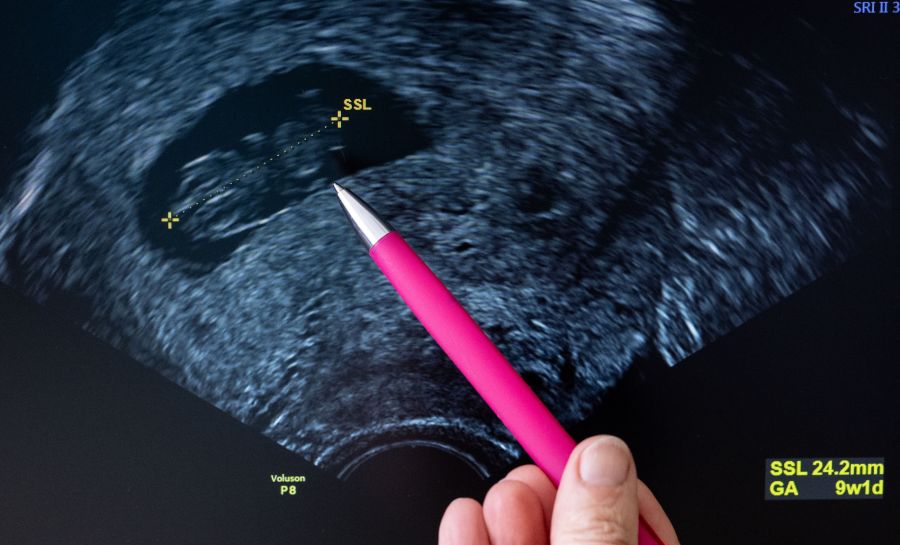

Dennoch brachte Molly im vergangenen Dezember Zwillinge zur Welt. Trotz der intensiven Schwangerschaft und einigen Wochen auf der Intensivstation sind beide Jungs heute gesund und munter.